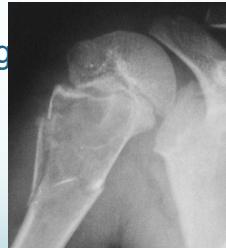

Osteochondroma (Exostosis)

- A common lesion

- Ends of long bone

- Bony overgrowth:

- Away from epiph. plate

- Covered by cartilage

- Growth:

- Stops when epiphysis close

- If continues later:

- ? Malignant transformation

Complications

- May fracture: becomes painful